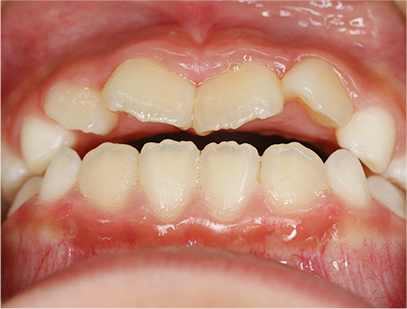

前歯部の開咬とデコボコ

前歯部が咬んでいないことを主訴として来院されました。精査、診断の結果「前歯部にデコボコを伴う開咬」と診断されました。

下の歯の裏側に舌が出ないように矯正装置を取り付け、そして上の歯には取り外しのできる矯正装置を装着して、側方に拡大を行います。

取り外しのできる矯正装置、舌が出せなくなる矯正装置(フェンス)

治療期間は、患者様の努力とお母さまの協力が得られて1年間で終了しました。